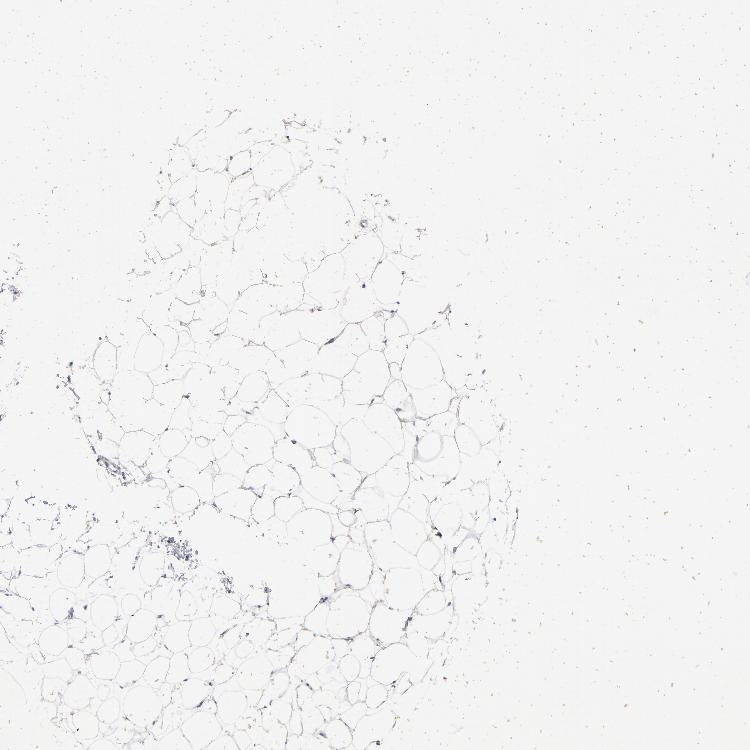

ADIPOSE TISSUE - Antibody stainingi

Antibody staining in the annotated cell types in the current human tissue is reported as not detected, low, medium, or high, based on conventional immunohistochemistry profiling in selected tissues. This score is based on the combination of the staining intensity and fraction of stained cells.

Each image is clickable and will lead to virtual microscopy that enables deeper exploration of all samples and also displays staining intensity scores, fraction scores and subcellular localization as well as patient and tissue information for each sample.

Antibody HPA003595Antibody HPA024006Antibody CAB009434Antibody CAB056159Antibody CAB080011

Adipocytes Not detectedNot detectedLowNot detectedNot detected